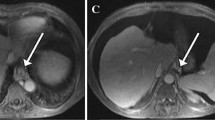

DCE-MRI acquisition and analysis were successfully performed in all patients. Figure 2 shows contrast-enhanced images and DCE-MRI curves in the liver and spleen for representative patients without PH and with PH and CSPH. With respect to modeled liver DCE-MRI parameters, liver uptake fraction fi and uptake rate ki both showed a significant negative correlation with HVPG (r = − 0.482, p = 0.003 and r = − 0.490, p = 0.003, respectively; Fig. 3). Model-free liver parameters upslope and uptake also were significantly negatively correlated with HVPG, but these correlations were slightly weaker than for the modeled parameters (r = − 0.398, p = 0.018 and r = − 0.418, p = 0.012, respectively; Fig. 3). None of the other evaluated liver DCE-MRI parameters correlated with HVPG (p value range 0.113–0.377). In terms of spleen parameters, ve showed a significant positive correlation with HVPG (r = 0.336, p = 0.048; Fig. 3), while other spleen DCE-MRI parameters showed non-significant correlations (p value range 0.149–0.579).

Liver uptake decreases with portal pressure. Representative post-contrast T1-weighted images, liver and spleen DCE-MRI data (blue), and fits (red) in (left) a 60-year-old male patient without PH (HVPG = 1 mmHg), (middle) a 72-year-old male patient with PH (HVPG = 9 mmHg), and (right) a 57-year-old male patient with CSPH (HVPG = 17 mmHg). The DCE-MRI parameters are shown in each plot. CSPH, clinically significant portal hypertension; HVPG, hepatic venous pressure gradient; PH, portal hypertension